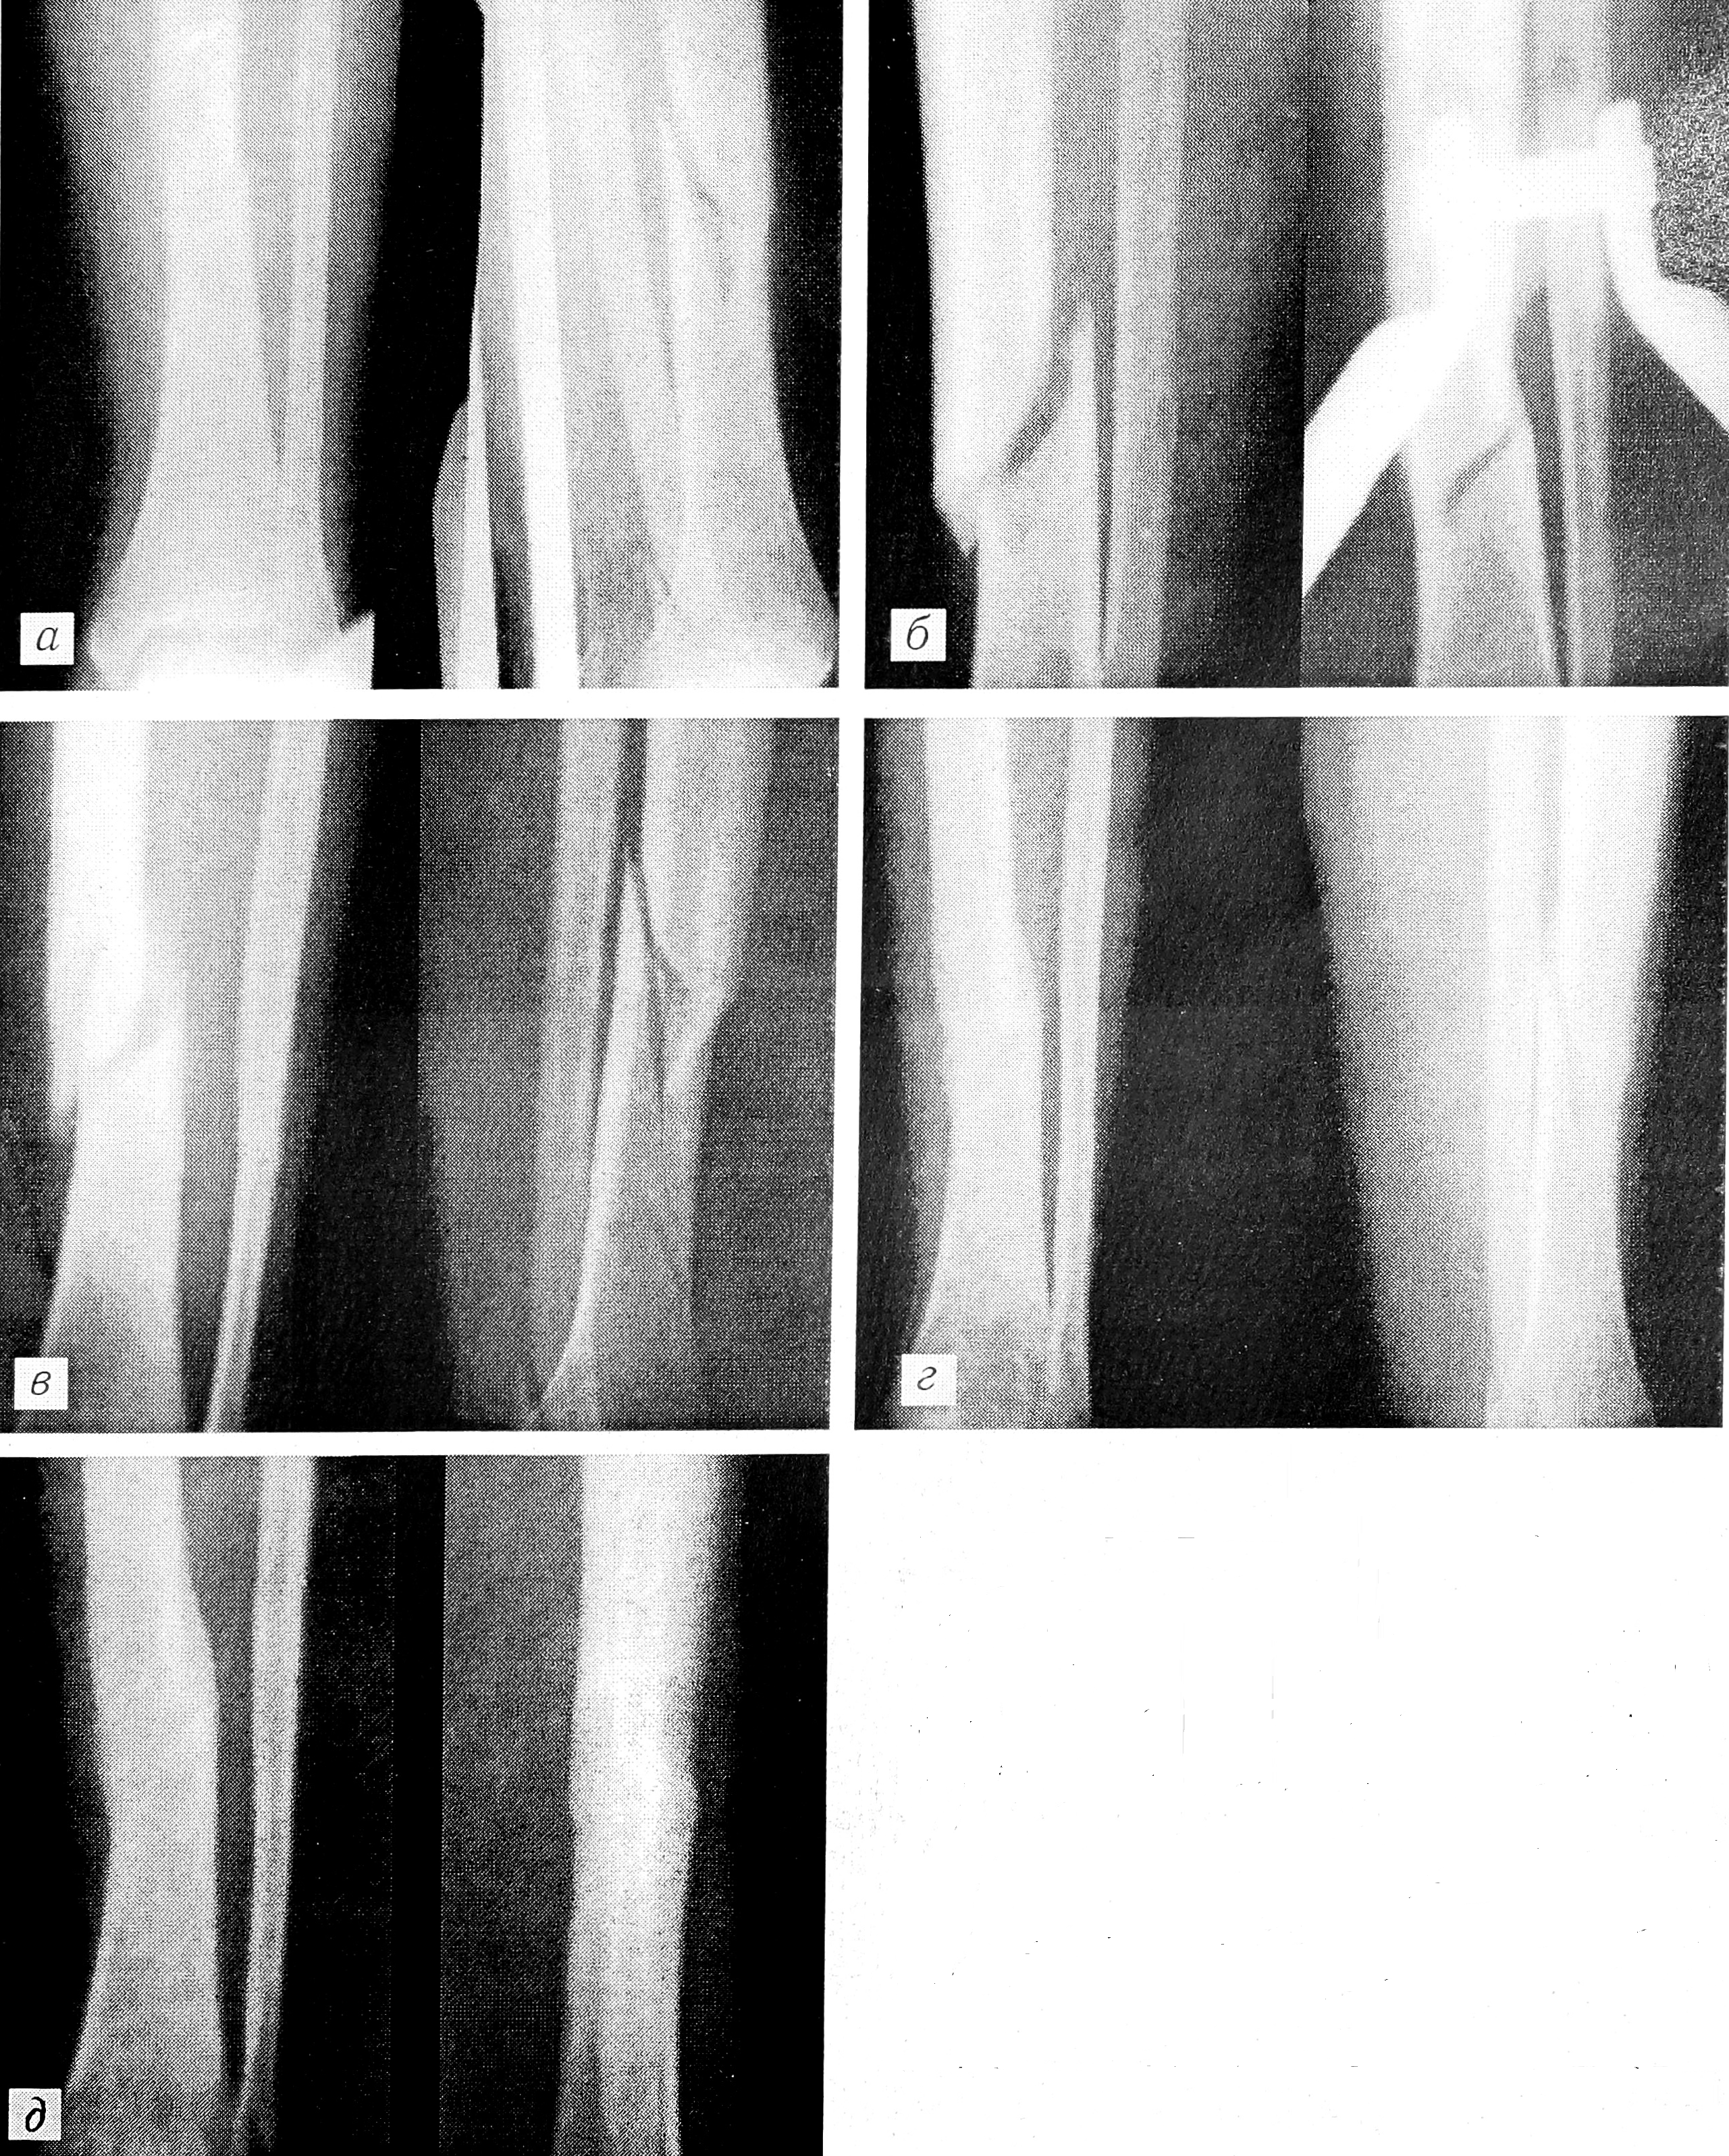

Сравнительный анализ рентгенограмм больных основной и контрольной групп показал более раннее (на 7—10 дней) появление признаков первичной мозоли после воздействия СМП (рис. 1 и 2 на вклейке). В контрольной группе у 5% больных отмечено несращение костей голени. Эти пациенты впоследствии были оперированы.

Рис. 2. Рентгенограммы больной с закрытым винтообразным переломом костей левой голени, леченным с применением сканирующего магнитного поля.

а — при поступлении; б — на 5-е сутки; в — через 3 мес (снята гипсовая повязка); г — через 4 мес; д — 5-й месяц после травмы: костная мозоль хорошая.